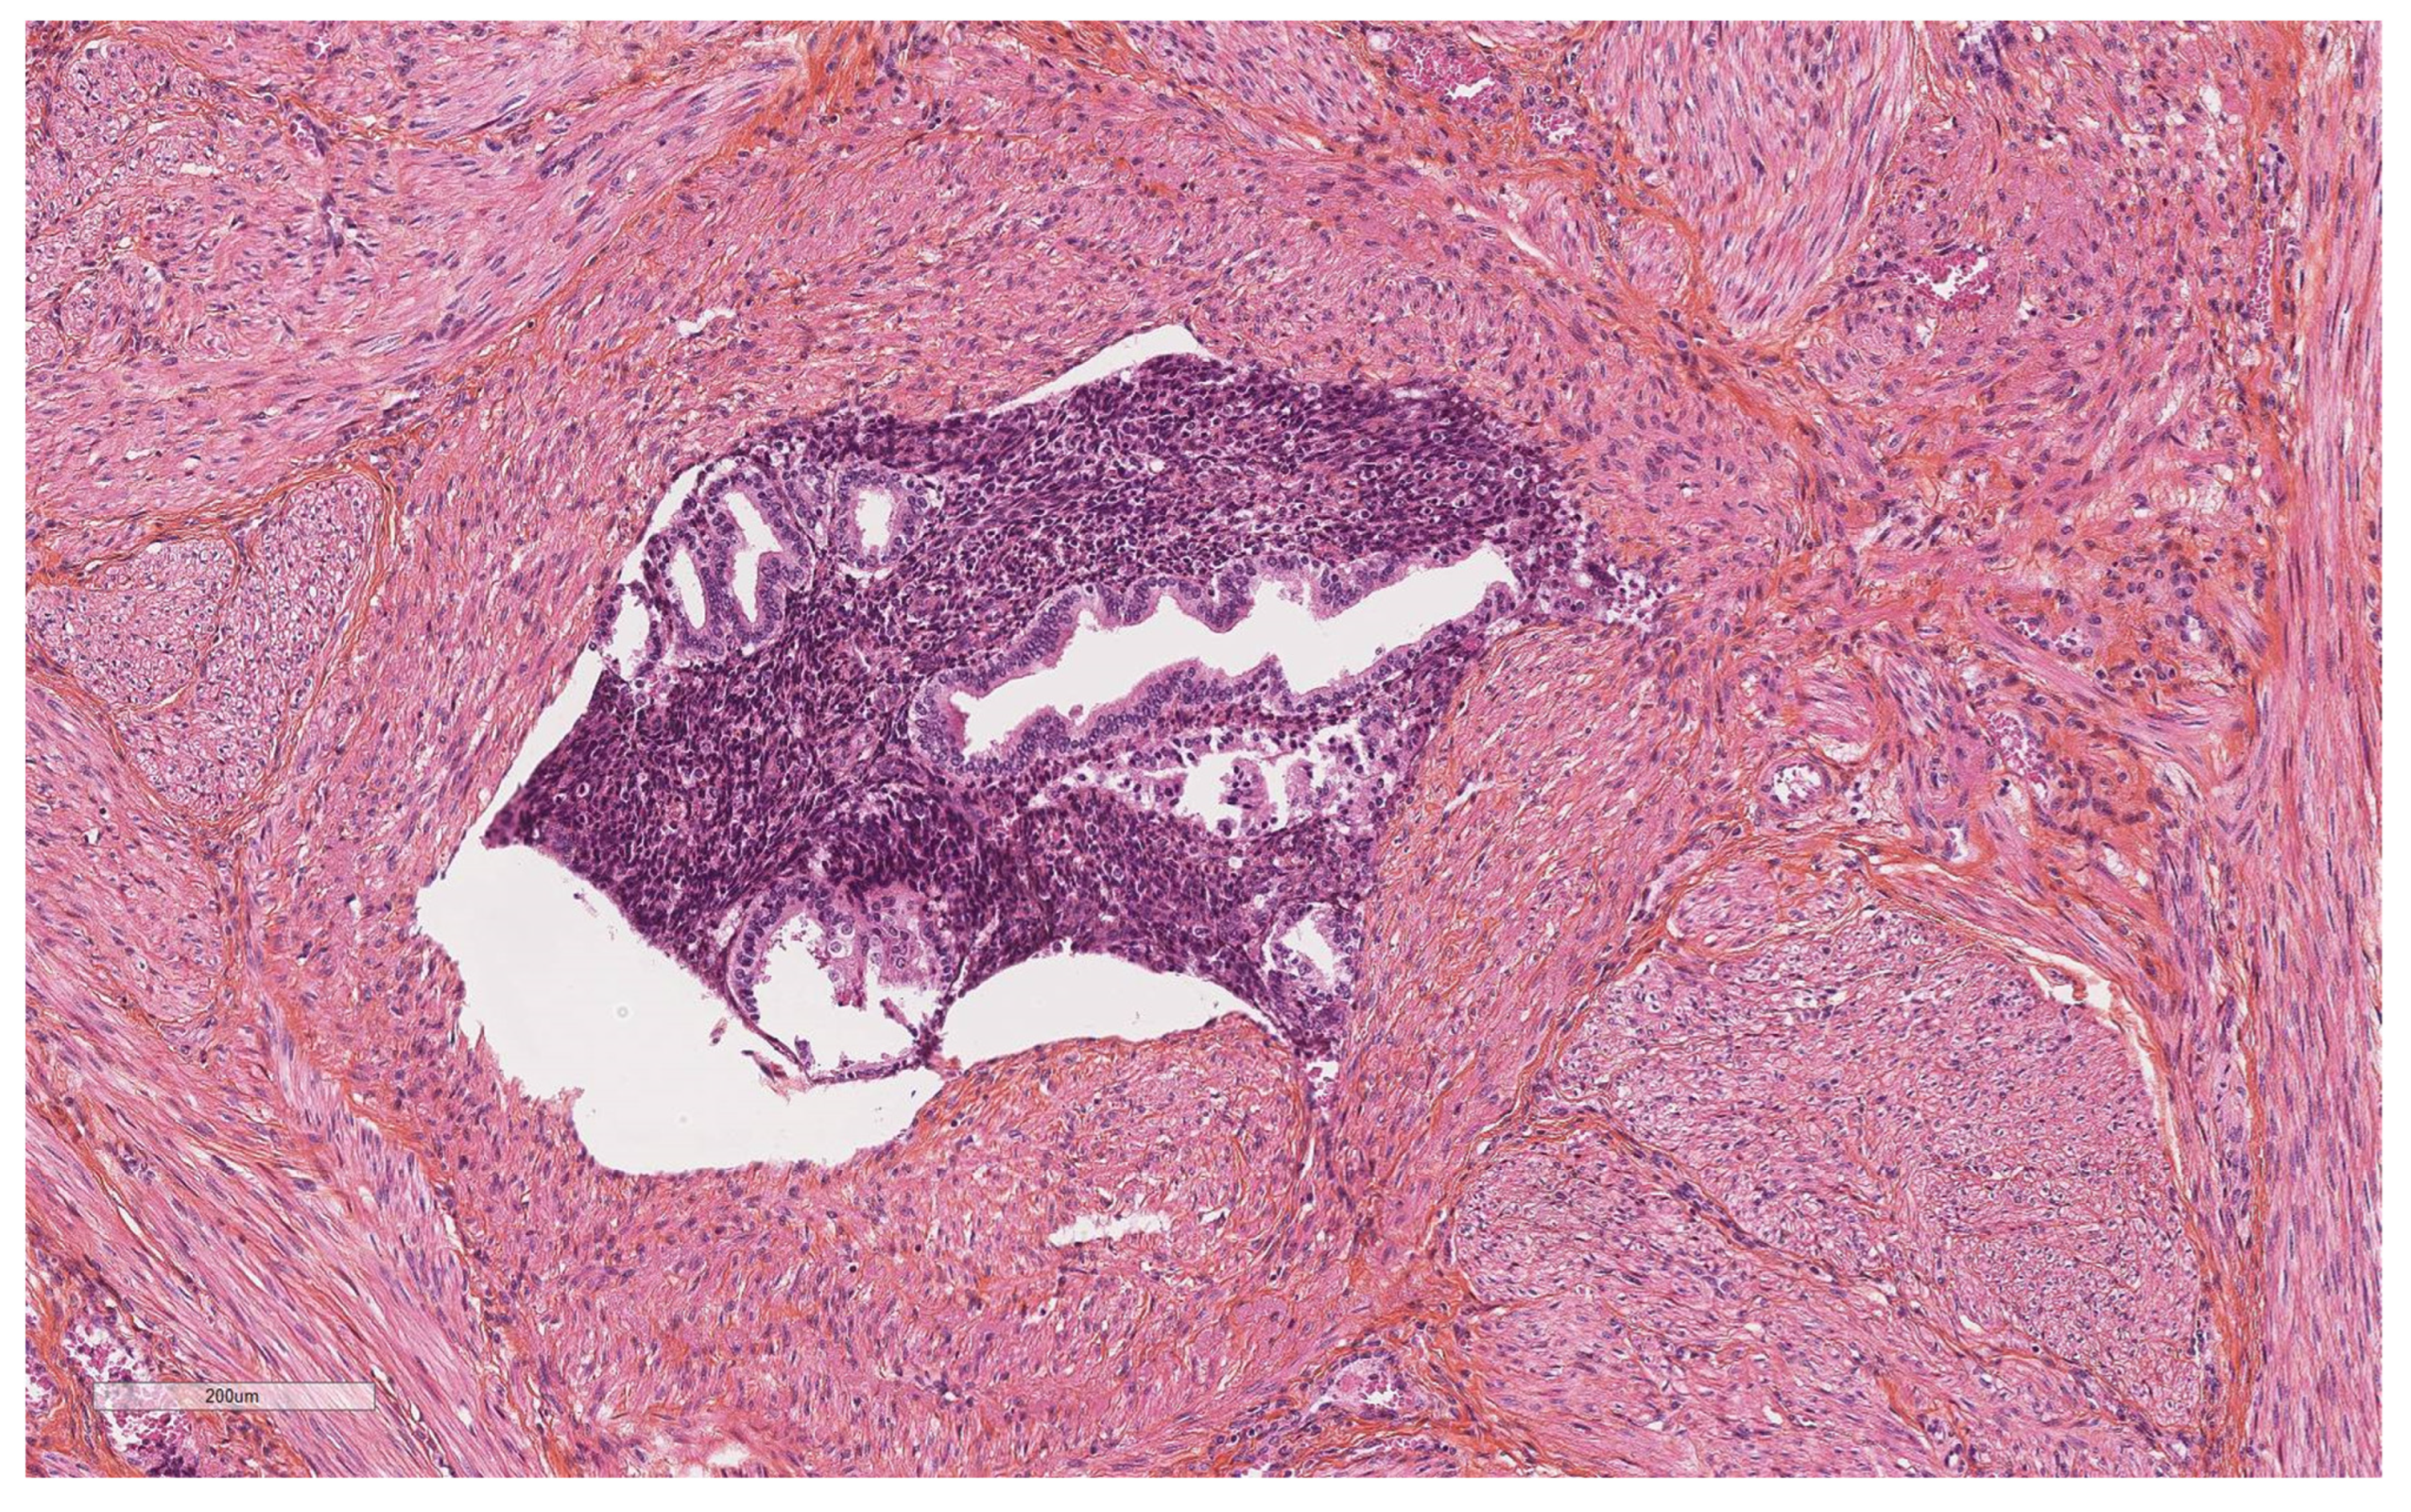

| Vascular pseudoinvasion | |

| Present | 14 (23.7) |

| Absent | 46 (76.6) |

| Myometrial clefts | |||

| Present | 10 | 6 | <0.001 |

| Absent | 4 | 40 | |